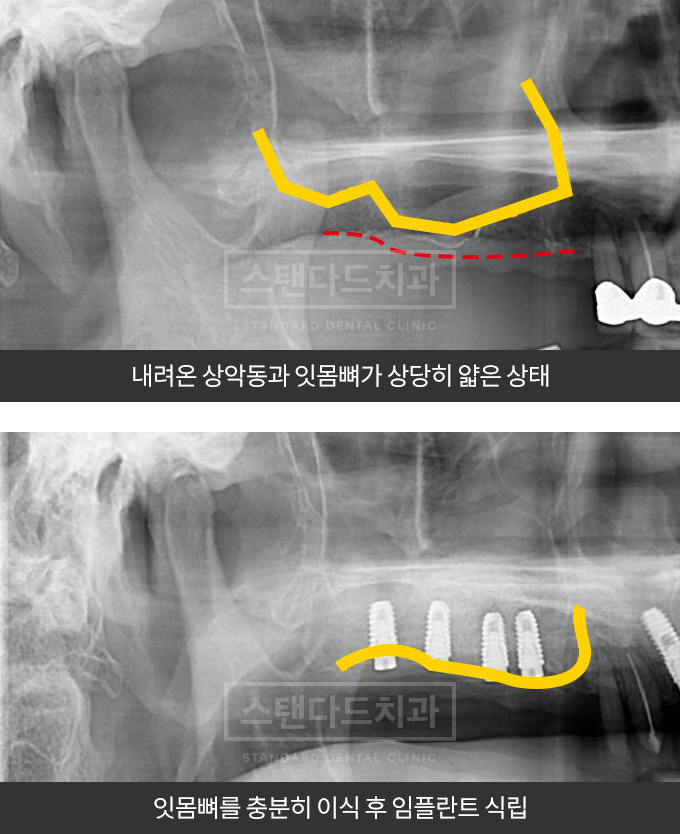

임플란트 성공과 실패의 척도 잇몸뼈를 만드는 기술

전체임플란트를 해야하는 환자들은 대부분 고령의 환자들로 오랜 틀니사용 또는 노화로 인해

치조골이 거의 남아있지 않는 경우가 많습니다.

이때, 치조골이식을 병행하여 잇몸뼈 재건 후 안정적인 임플란트 식립을 하고 있습니다.